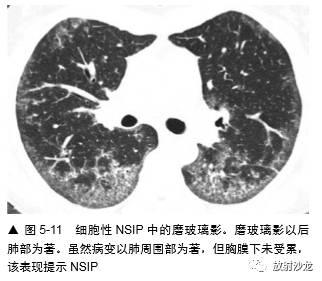

亚急性或慢性症状病例中磨玻璃影最常见的病因包括(表 5-1):间质性肺炎,如非特异性间 质性肺炎(NSIP)(图 5-8,图5-11),特发性 或其他特异性疾病,如硬皮病或其他胶原血管病,脱屑性间质性肺炎(DIP)(图 5-12) ,呼吸细支气管炎-间质性肺疾病(RB-ILD),过敏性肺炎(HP)(图 5-5,5-13), 机化性肺炎(OP),药物反应,慢 性嗜酸性肺炎(图 5-14),淋巴样间质性 肺炎(LIP),Churg-Strauss综合征, 类脂质肺炎(图5-15)和慢性或反复性吸入性肺炎,非黏液性和黏液性肺腺癌(图5-16) , 结节病,和肺泡蛋白沉着症(PAP)(图 5-17)。

在有磨玻璃影的病例中,组织学异常的类型 根据疾病的典型组织学表现而异,无特异性组织学改变(表 5-2)。在 NSIP、硬皮病或 其他胶原血管病病例中,许多研究曾结合CT 上 的磨玻璃影和活检结果、治疗反应和病例的生存期。在间质性肺炎病例的组织学研 究中曾显示,大部分磨玻璃影和肺泡壁或肺泡内炎症相关。例如,在一项Wells 等的硬皮病研究中,HRCT 上的致密度增加和7 例活检中4例的明显炎症相关,而在HRCT 上的网影中,13 例中12 例为纤维化。另一项14 例HRCT 表现为 磨玻璃影的特发性肺纤维化(IPF)病例中,活检 12 例有炎症。在寻常性间质性肺炎(UIP)病 例中,磨玻璃影伴有不等的肺纤维化;有磨玻璃 影的DIP 病例在很大程度上反映肺泡内有巨噬细胞。